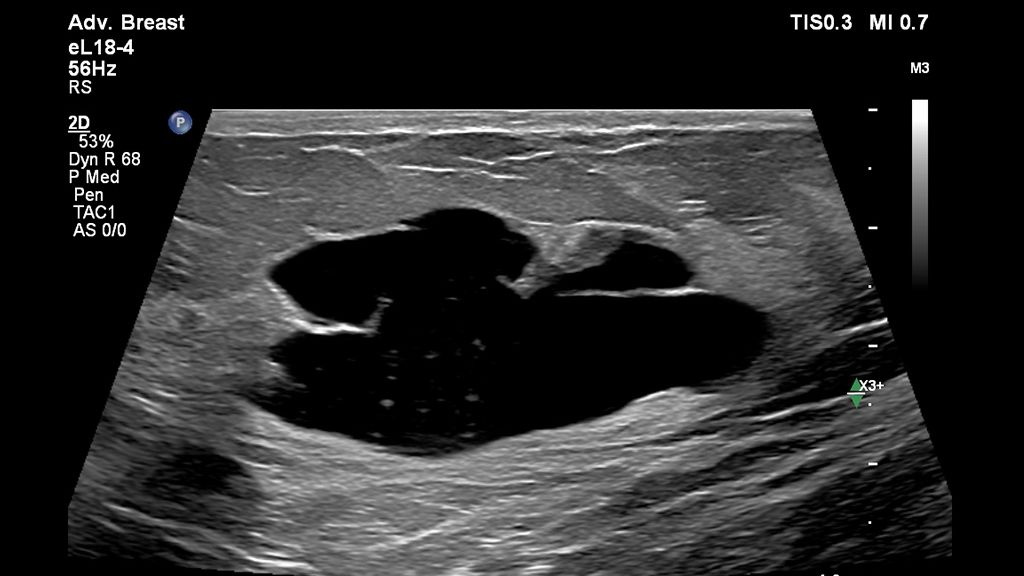

• Superficial Cyst with Calcifications

Superficial Cyst with Calcifications

• EPIQ Elite Elevate with L26-8 probe for Breast with Superficial Cyst

EPIQ Elite Elevate with L26-8 probe for Breast with Superficial Cyst